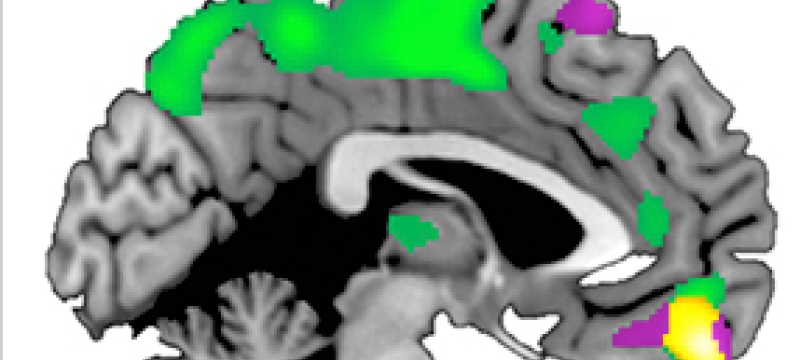

Compelling new research from the department of psychology on how brain structure in people differs according to how trusting people are of others: The research may have implications for future treatments of psychological conditions such as autism, said the study's lead author Brian Haas, an…